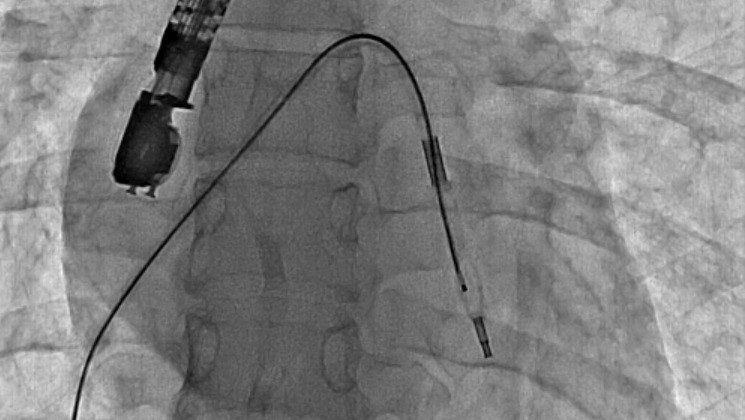

Eskişehir Şehir Hastanesi’nde ilk defa mitral balon operasyonu yapıldı. Operasyon, anjiyografi cihazı ile adım adım kaydedildi.

Eskişehir Şehir Hastanesi’nde Kardiyoloji Uzmanı Dr. Mehmet Özgeyik ve 4 kişilik ekibi tarafından ilk defa mitral balon operasyonu yapıldı. Türkiye’de az sayıda yapılan kalp kapağı balon işlemiyle yeni anne olmuş genç bir hasta sağlığına kavuştu. Bu sayede hastalar ameliyat olmaktan, ömür boyu kan sulandırıcı ilaçlar kullanmaktan ve metal bir kalp kapağı ile yaşamaktan kurtuluyor.

Gerçekleşen başarılı operasyon hakkında konuşan Kardiyoloji Uzmanı Dr. Mehmet Özgeyik, “Bu işlemi genellikle kalp kapaklarında ciddi darlık olan genç hastaların kişilere uyguluyoruz. Buradaki amacımız ameliyat olmadan, kasıktan küçük iki damar yolu açarak hastalarımızın kapak darlıklarını uzun süreli olarak genişletmeyi hedefliyoruz. Burada 23 yaşında yeni anne olmuş genç bir hastamıza müdahale yaptık. Hastamız ya kapak ameliyatı olacaktı ya da bu işlem sayesinde kapak darlığını aşmayı planlıyorduk. İşlem gayet başarılı oldu. Hastamızın kapak darlığını genişlettik. En azından 10-15 sene boyunca ameliyata gerek kalmadan hastamızı ilaç tedavisiyle takip etmeyi planlıyoruz” diye konuştu.

Cerrahi operasyonlar yerine mitral balon işlemiyle hastaları sağlıklarına kavuşturmak istediklerini aktaran Dr. Özgeyik, “Hastanemizde ilk kez yapılan bir işlem. Bu işlem için uygun hasta bulmak biraz zor oluyor çünkü çok sık yapılan bir işlem değil. Fakat gelecekte hasta portföyümüzün de artması ile birlikte daha sık yapmayı planlıyoruz. En azından hastalarımızı büyük bir cerrahi operasyona vermeden böyle küçük işlemlerle hayat kalitelerini artırmayı planlıyoruz. Hastamız ameliyata gitmiş olsaydı büyük bir operasyon geçirmiş olacaktı. Göğüs bölgesinde büyük bir kesiğe maruz kalacaktı. Aynı zamanda ömür boyu kullanması gereken farklı ilaçlar olacaktı. Hasta kendisine ait olmayan metal bir kapakla yaşamak zorunda kalacaktı. Biz bu işlemde hastaya kasıktan iki tane damar yolu açtık. Hastaya neşter ile kesme işlemi uygulamaktan kurtardık. Ayrıca hastanın hayatı boyunca kullanacağı kan sulandırıcı ilaçları uzunca bir süre ertelemiş olduk. En önemlisi de hastanın kendi kalp kapağını kullanmasını sağlamış olduk ve metal kapak yükünden kurtulmuş oldu” şeklinde konuştu.